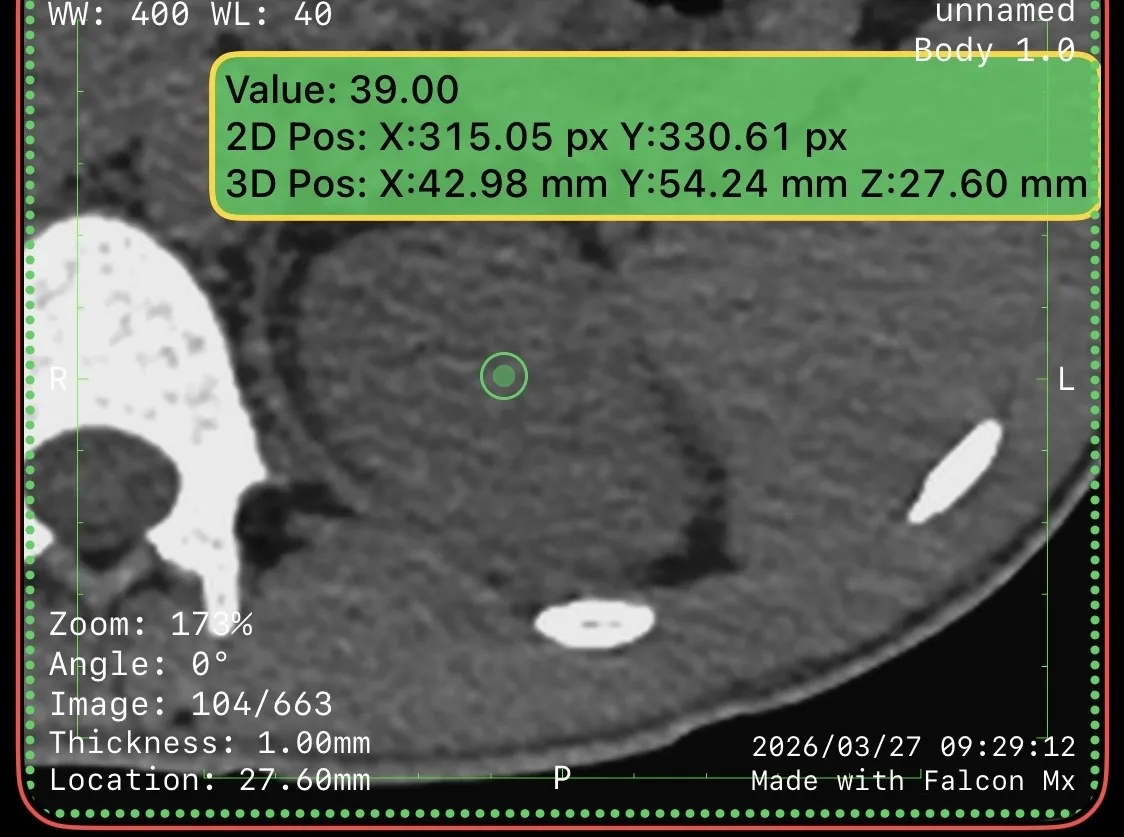

Пациент 27 лет. Две недели назад ударно-волновая литотрипсия. Неделю назад резкое повышение температуры тела, боли в боку. Повторная госпитализация. Установлен стент в левый мочеточник. Нарушения оттока мочи нет. На компьютерных томограммах левосторонний бактериальный нефрит, в верхнем полюсе левой почки – то, что иногда называют карбункул: воспалительный инфильтрат без формирования абсцесса (в англоязычной литературе называется нефрония). Принято решение продолжать антибиотикотерапию.